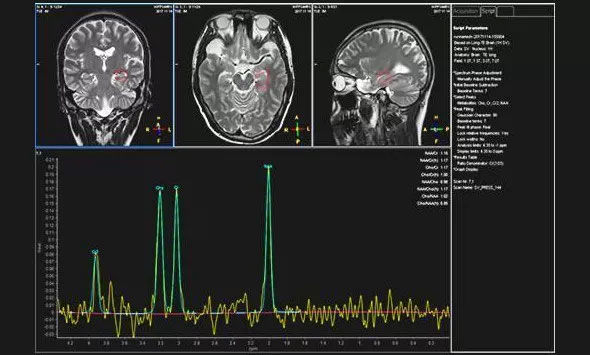

▲患者异常的波谱图

近日,为求进一步治疗,患者就诊于上海蓝十字脑科医院。为完善相关检查,医院为袁女士进行了头部MRI增强扫描,检查结果与之前的影像检查一致。为了进一步明确病灶区,医院为患者进行24小时脑电监测,据脑电监测主任崔丽华介绍,患者为异常视频脑电图,左侧额极、左侧颞叶多量尖慢波并发,监测期间患者癫痫还发作了3次。

据吴治群博士介绍,袁女士的癫痫比较特殊,她不单单是左侧颞叶(海马区)囊实性占位引起的癫痫,同时还合并额叶癫痫,这种情况在临床中也是不多见的。对于继发性癫痫的治疗,吴治群博士指出,首先要去除引起患者癫痫的因素,这样对因治疗效果才会更好;而袁女士左侧颞叶(海马区)明显占位,属于继发性癫痫,病因明确,通常首选手术治疗癫痫。